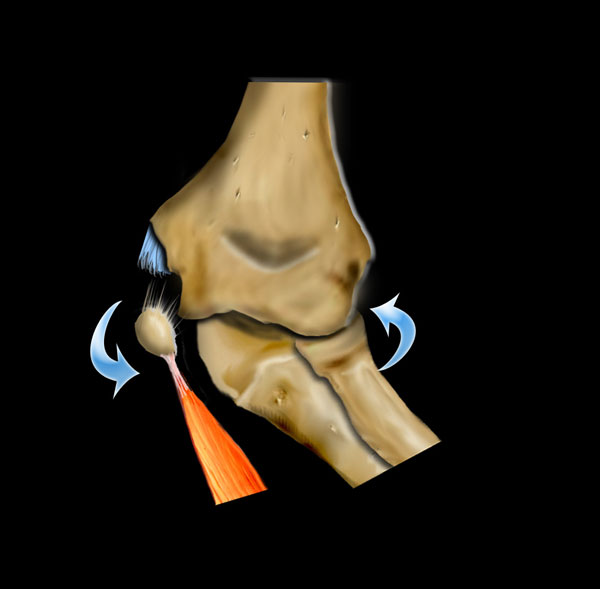

Fracture mechanism

Hyperextension

Chấn thương khớp khuỷu tay thường là kết quả của tình trạng duỗi quá mức hoặc vẹo ngoài quá mức do ngã chống tay ra phía trước.

Extreme valgus

Cơ chế gãy xương quan trọng khác là tình trạng valgus cùi chỏ quá mức.

Khuỷu tay bình thường đã có tư thế valgus sẵn.

Khi trẻ ngã chống tay với cánh tay duỗi thẳng, điều này có thể dẫn đến valgus quá mức.

Ở phía ngoài, điều này có thể dẫn đến trật khớp hoặc gãy xương quay có hoặc không kèm theo tổn thương mỏm khuỷu.

Khi lực tác động nhiều hơn lên xương cánh tay, tình trạng valgus quá mức sẽ dẫn đến gãy lồi cầu ngoài.

Ở phía trong, lực valgus có thể dẫn đến bong lồi cầu trong.

Đôi khi lồi cầu trong bị kẹt trong khớp.

Do tư thế valgus của khuỷu tay bình thường, bong lồi cầu ngoài sẽ ít gặp hơn.